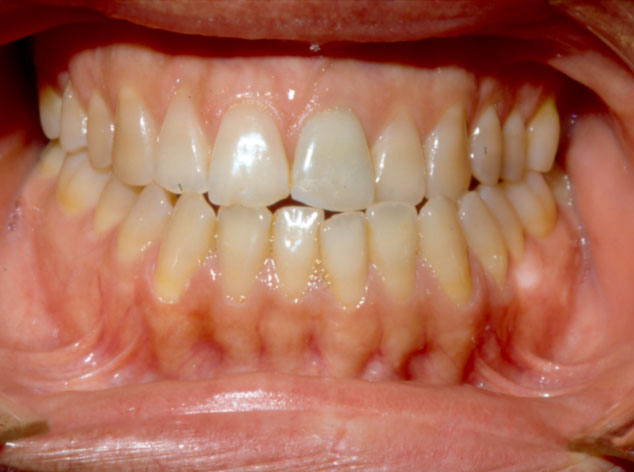

En la imagen intraoral se confirma el prognatismo mandibular, una oclusión en clase 3. Mordida de borde a borde con cierta asimetría en la que se aprecia una desviación de la línea media de casi dos o tres milímetros hacia la izquierda.